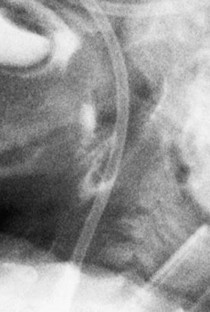

Fig. 2